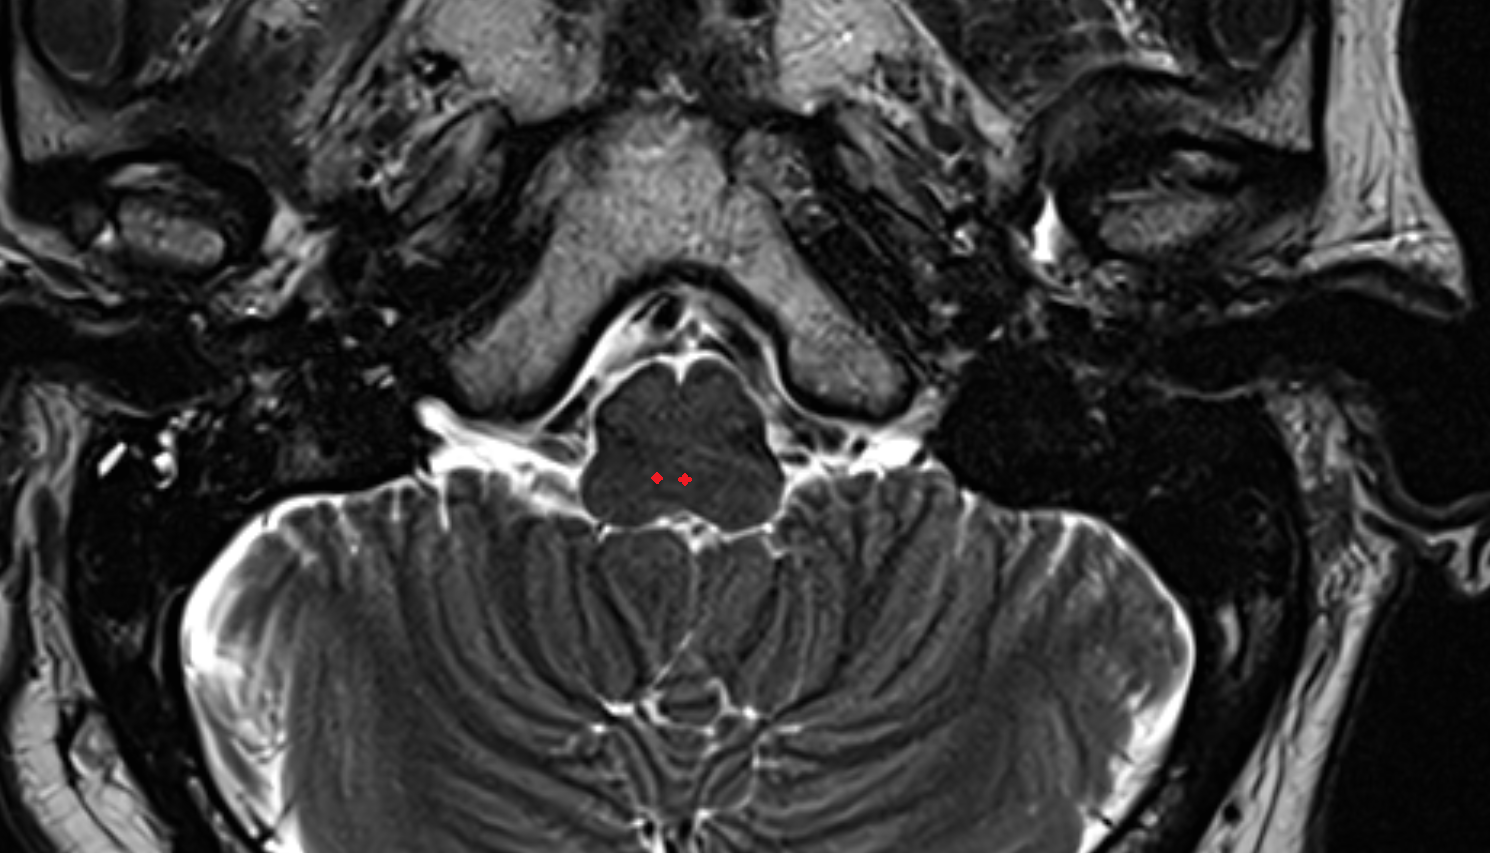

- Pons

- Premedullary cistern

- Cerebellopontine cistern

- Pontocerebellar cistern

- Prepontine cistern